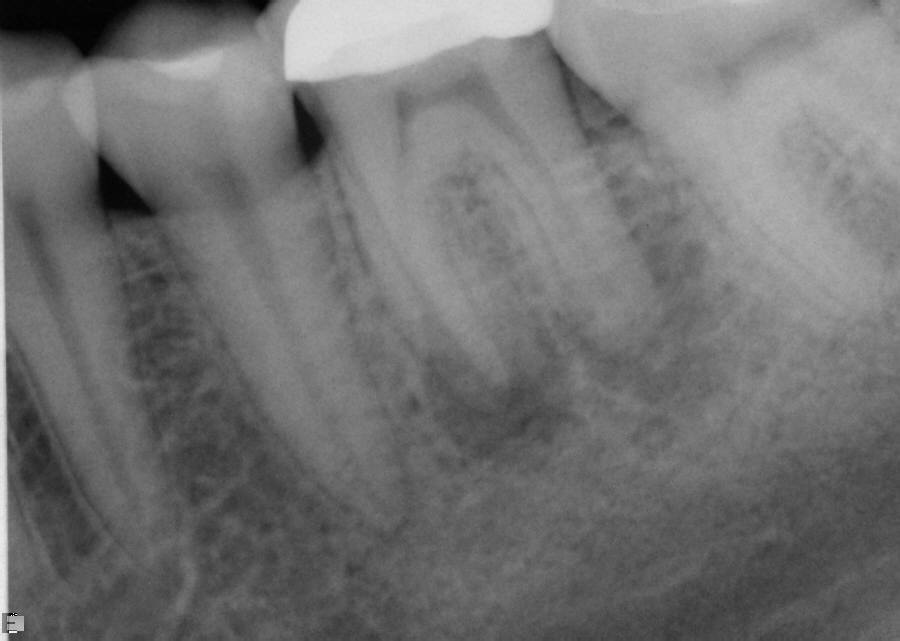

Excellent diagnosis essentially begins with two fundamental components: a doctor willing to listen to the patient’s chief complaint, and proper diagnostic tools. Among the most important tools are a precise periapical radiograph (PA) and bitewing (BW). Although a PA is often enough to provide an accurate portrayal of the patient’s condition, sometimes it alone does not suffice. Figure 1, Figure 2, and Figure 3 demonstrate a case that illustrates this point clearly. Despite two acceptable PAs (Figure 1 and Figure 2), it is difficult to assess the source of the patient’s pain to temperature. However, the BW radiograph Figure 3 provides significantly more clarity than either of the two PAs. The BW depicts localized bone loss (around tooth No. 2), a pulp stone (No. 2), a flat occlusion, numerous calcified canals, multiple restorations in tooth No. 30, and gross decay especially on tooth No. 3, which is the source of the patient’s pain to temperature. In this instance these images depict how much more useful a BW can be than just a conventional PA.